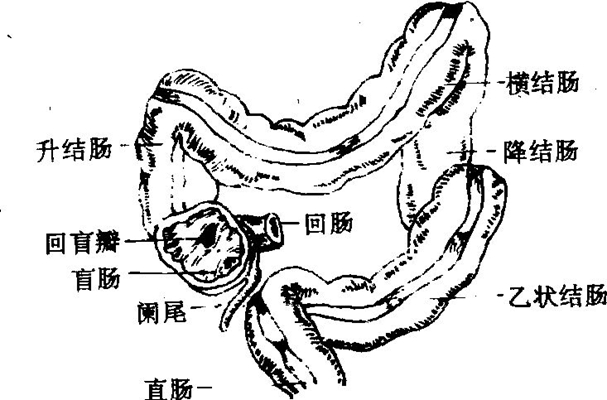

盲腸炎圖片

盲腸的位置 (50)

盲腸的位置 (6)

盲腸的位置 (7)

盲腸的位置 (8)

盲腸的位置 (9)

盲腸的位置 (46)

盲腸的位置 (47)

盲腸的位置 (48)

盲腸的位置 (49)

盲腸的位置 (5)